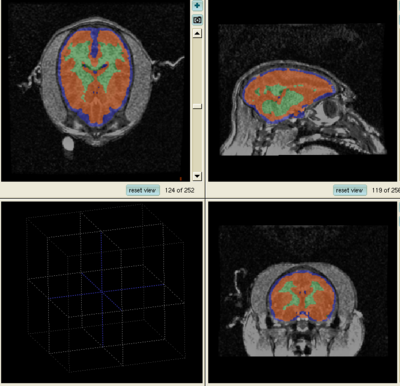

Segmentation Results

1. The results for the best and worst segmentations are shown in the following. For each subject, the first figure shows the alignment of Gray matter atlas (these will be changed to checker board figures aligning target and the whole brain atlas soon) with the brains, and the second figure shows the segmentation results.

Best Segmentation: Oscar